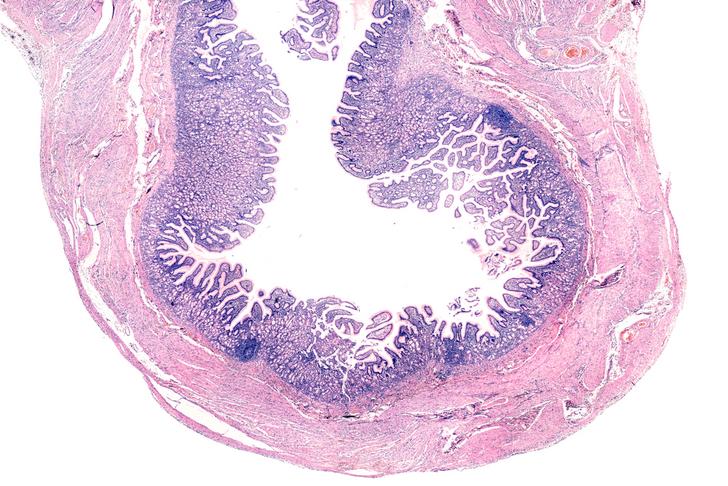

Inflammatory Bowel Disease

Inflammatory bowel disease (IBD) is a group of disorders that cause chronic inflammation in the digestive tract, including Crohn’s disease and ulcerative colitis[[6]]. Symptoms can include abdominal pain, diarrhea, weight loss, and bloody stool. Treatment options may involve medications to reduce inflammation, dietary changes, and surgery in severe cases.